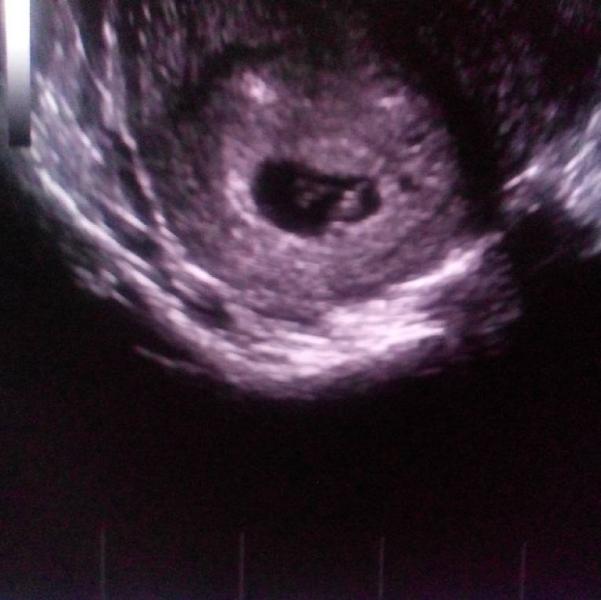

Сегодня была на узи. какое счастье впервые слышать сердце своего еще совсем маленького малыша.